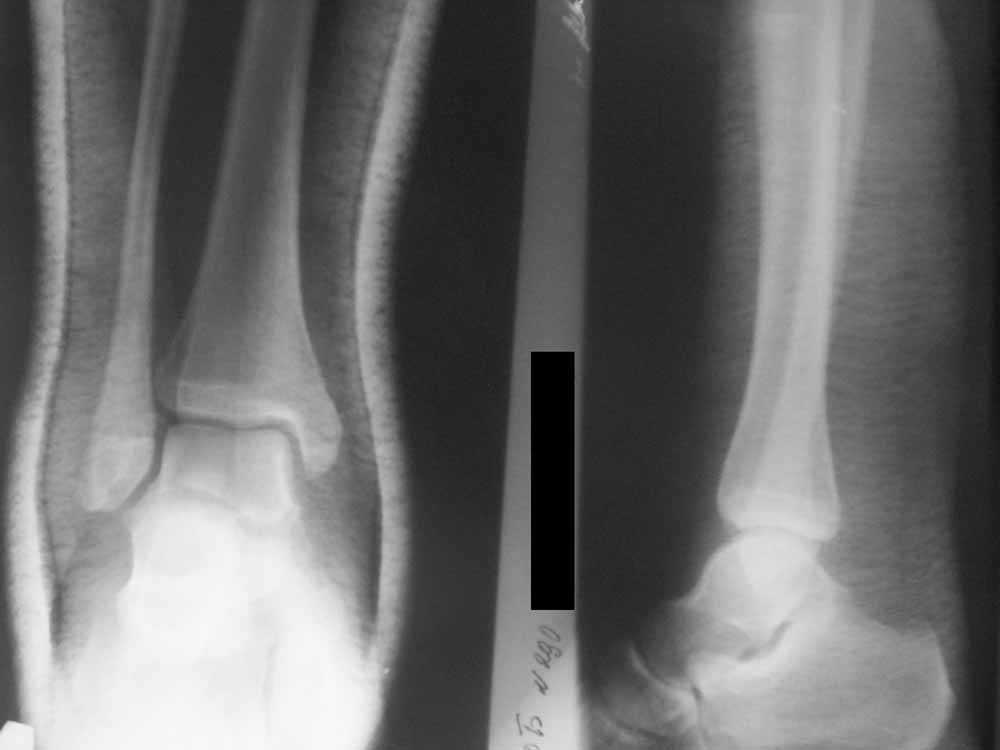

Двухлодыжечный перелом + разрыв синдесмоза - оперировать или нет?

Уважаемые коллеги! Помогите, пожалуйста, советом! Пациентка 14 лет. Двухлодыжечный перелом с (как нам кажется) повреждением межберцового синдесмоза.

Вопрос один: оперировать или оставить "как есть" в гипсе? Не будет ли в дальнейшем проблем с суставом.